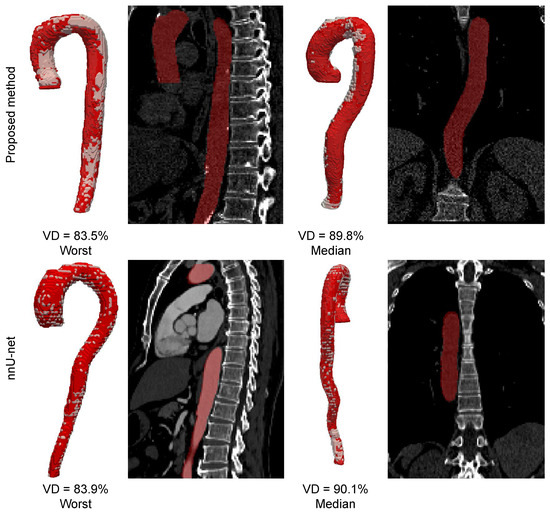

We compared the segmentation quality of the proposed method with the segmentation quality achieved by the nnU-Net method [78]. The nnU-Net is a strong baseline method that automatically configures an optimal convolutional neural network architecture for a given segmentation task based on data analysis. For training, nnU-Net employs the Adam optimizer with an initial learning rate of 3 × 10 4 , and automatically reduces the learning rate every 30 epochs twice if no improvement in performance is observed. One epoch is defined as an iteration over 250 training batches, and training is performed for up to a maximum of 1000 epochs. To augment the training dataset, nnU-Net applies various techniques such as random rotations, random scaling, random elastic deformations, gamma correction augmentation, and mirroring. The results of the nnU-Net method and our proposed method are presented in Table A3. Examples of segmentation results are shown in Figure A1. Based on the experimental results, we conclude that the segmentation performance of both methods is comparable.

Figure A1. Examples of ground truth segmentation masks (shown in white) and segmentation results (shown in red) for the proposed method and nnU-net.